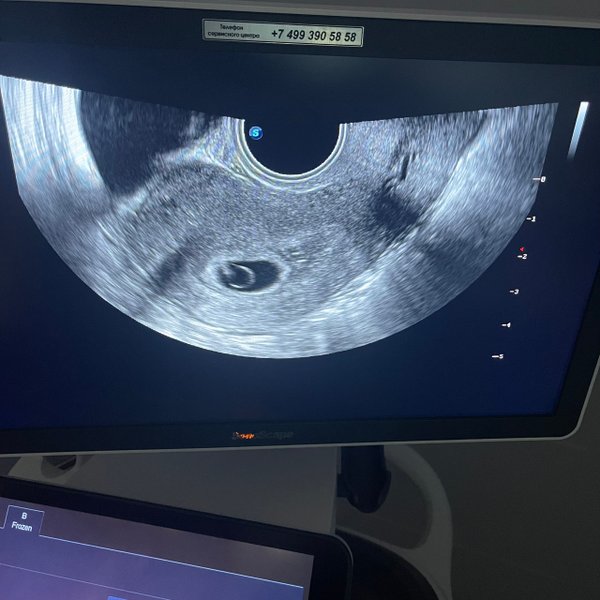

Бородулина Наталья (Врач УЗИ, Косметология) (05.12.2024): #беременность малого срока (продолжение..) ⠀ Что будет сначала видно на #узи осмотре Кто ходил в ранних сроках на узи знает, что эмбрион виден не сразу. Сначала видно плодное яйцо, потом появляется желточный мешочек, и последним появляется эмбрион. ⠀ Плодное яйцо в матке начинает достоверно визуализироваться при размере от 4 мм. ⠀ ️С какой скоростью должно расти плодное яйцо в норме? 0,8—1,2 мм/сут ⠀ ️Когда появляется сердцебиение у эмбриона? При размере его 5—7 мм! ⠀ ️Когда дол… — Читать дальше

жен появиться эмбрион в плодном яйце? При диаметре плодного яйца 16—24 мм Вот такие дела

Бородулина Наталья (Врач УЗИ, Косметология) (29.11.2024): Малыш с «шариком» ️ долгожданная беременность..маленькое счастье да-да, даже в такой маленький срок, сердечко УЖЕ слышно

Угадайте по фото #УЗИ, кто тут ( Шутка, конечно, рано еще Но верить в чудеса можно уже сейчас).

Поделитесь в комментариях своими первыми

#фото «горошков», «фасолинок» и «эмбриончиков» устроим галерею самого начала жизни ️

#Сочельник… время чудес вы уже загадали заветное желание ⁉️ На небе разглядели первую звезду?

На фото УЗИ 4 недель а если подключить фантазию, что видите? Я вижу малыша, который держит шарик